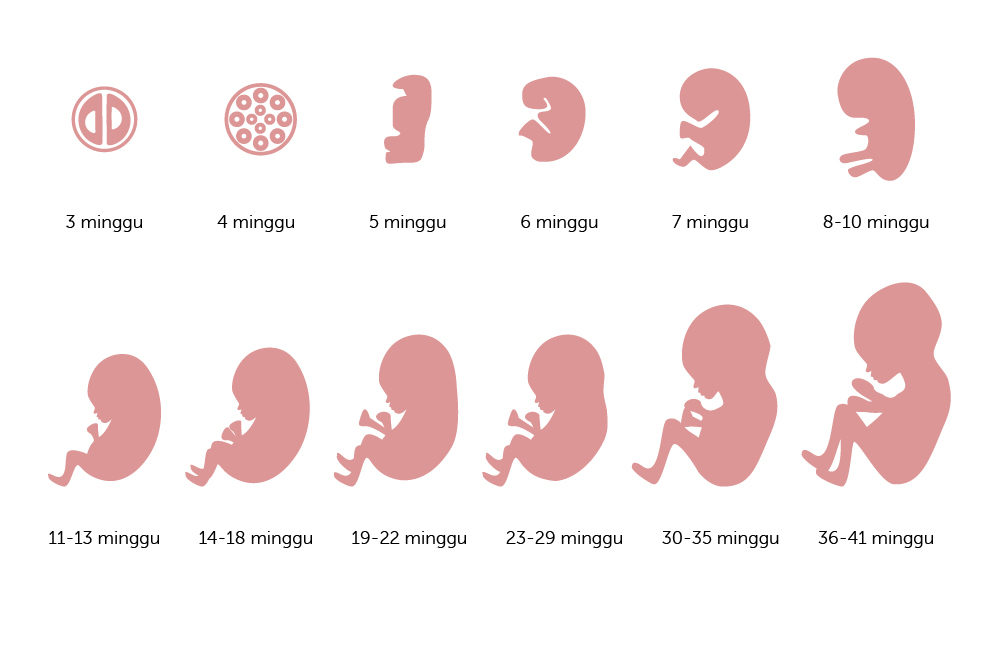

Ini Perkembangan Bayi Dalam Kandungan Dari Minggu Ke Minggu Alodokter

Ini Perkembangan Bayi Dalam Kandungan Dari Minggu Ke Minggu Alodokter

Pertambahan Berat Janin Normal Di Tiap Trimester Kehamilan

Pertambahan Berat Janin Normal Di Tiap Trimester Kehamilan

Ini Perkembangan Bayi Dalam Kandungan Dari Minggu Ke Minggu Alodokter

Ini Perkembangan Bayi Dalam Kandungan Dari Minggu Ke Minggu Alodokter